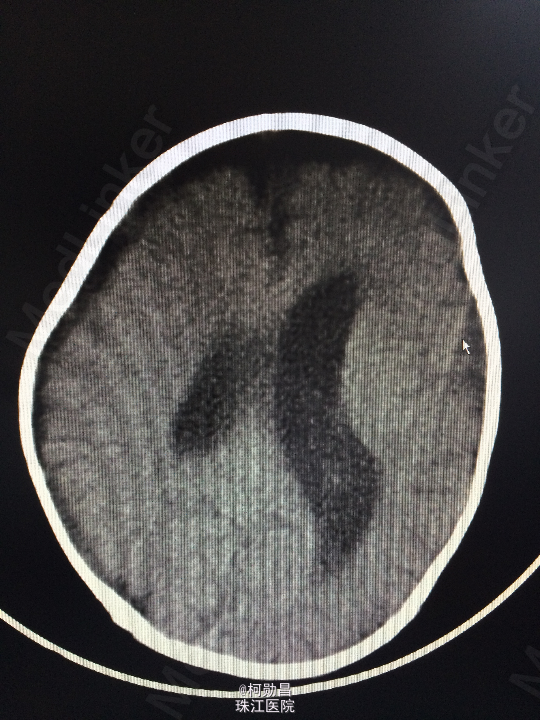

主诉:发热10天,抽搐3天 病史:患儿出生后8个月,因“发热10天,抽搐3天”入院,入院时体温39.3℃,神志不清,反应差。四肢肌张力增高,以双上肢肌力增高明显。病理征未引出。

查体:神志不清,四肢肌力增高 辅助检查:头颅CT提示脑积水并脑脊液外渗,幕上脑室扩张,右侧额颞叶硬膜下脑脊

诊断:化脓性脑膜炎伴脑积水 处理:予内科抗感染治疗,后行脑室腹腔引流术。